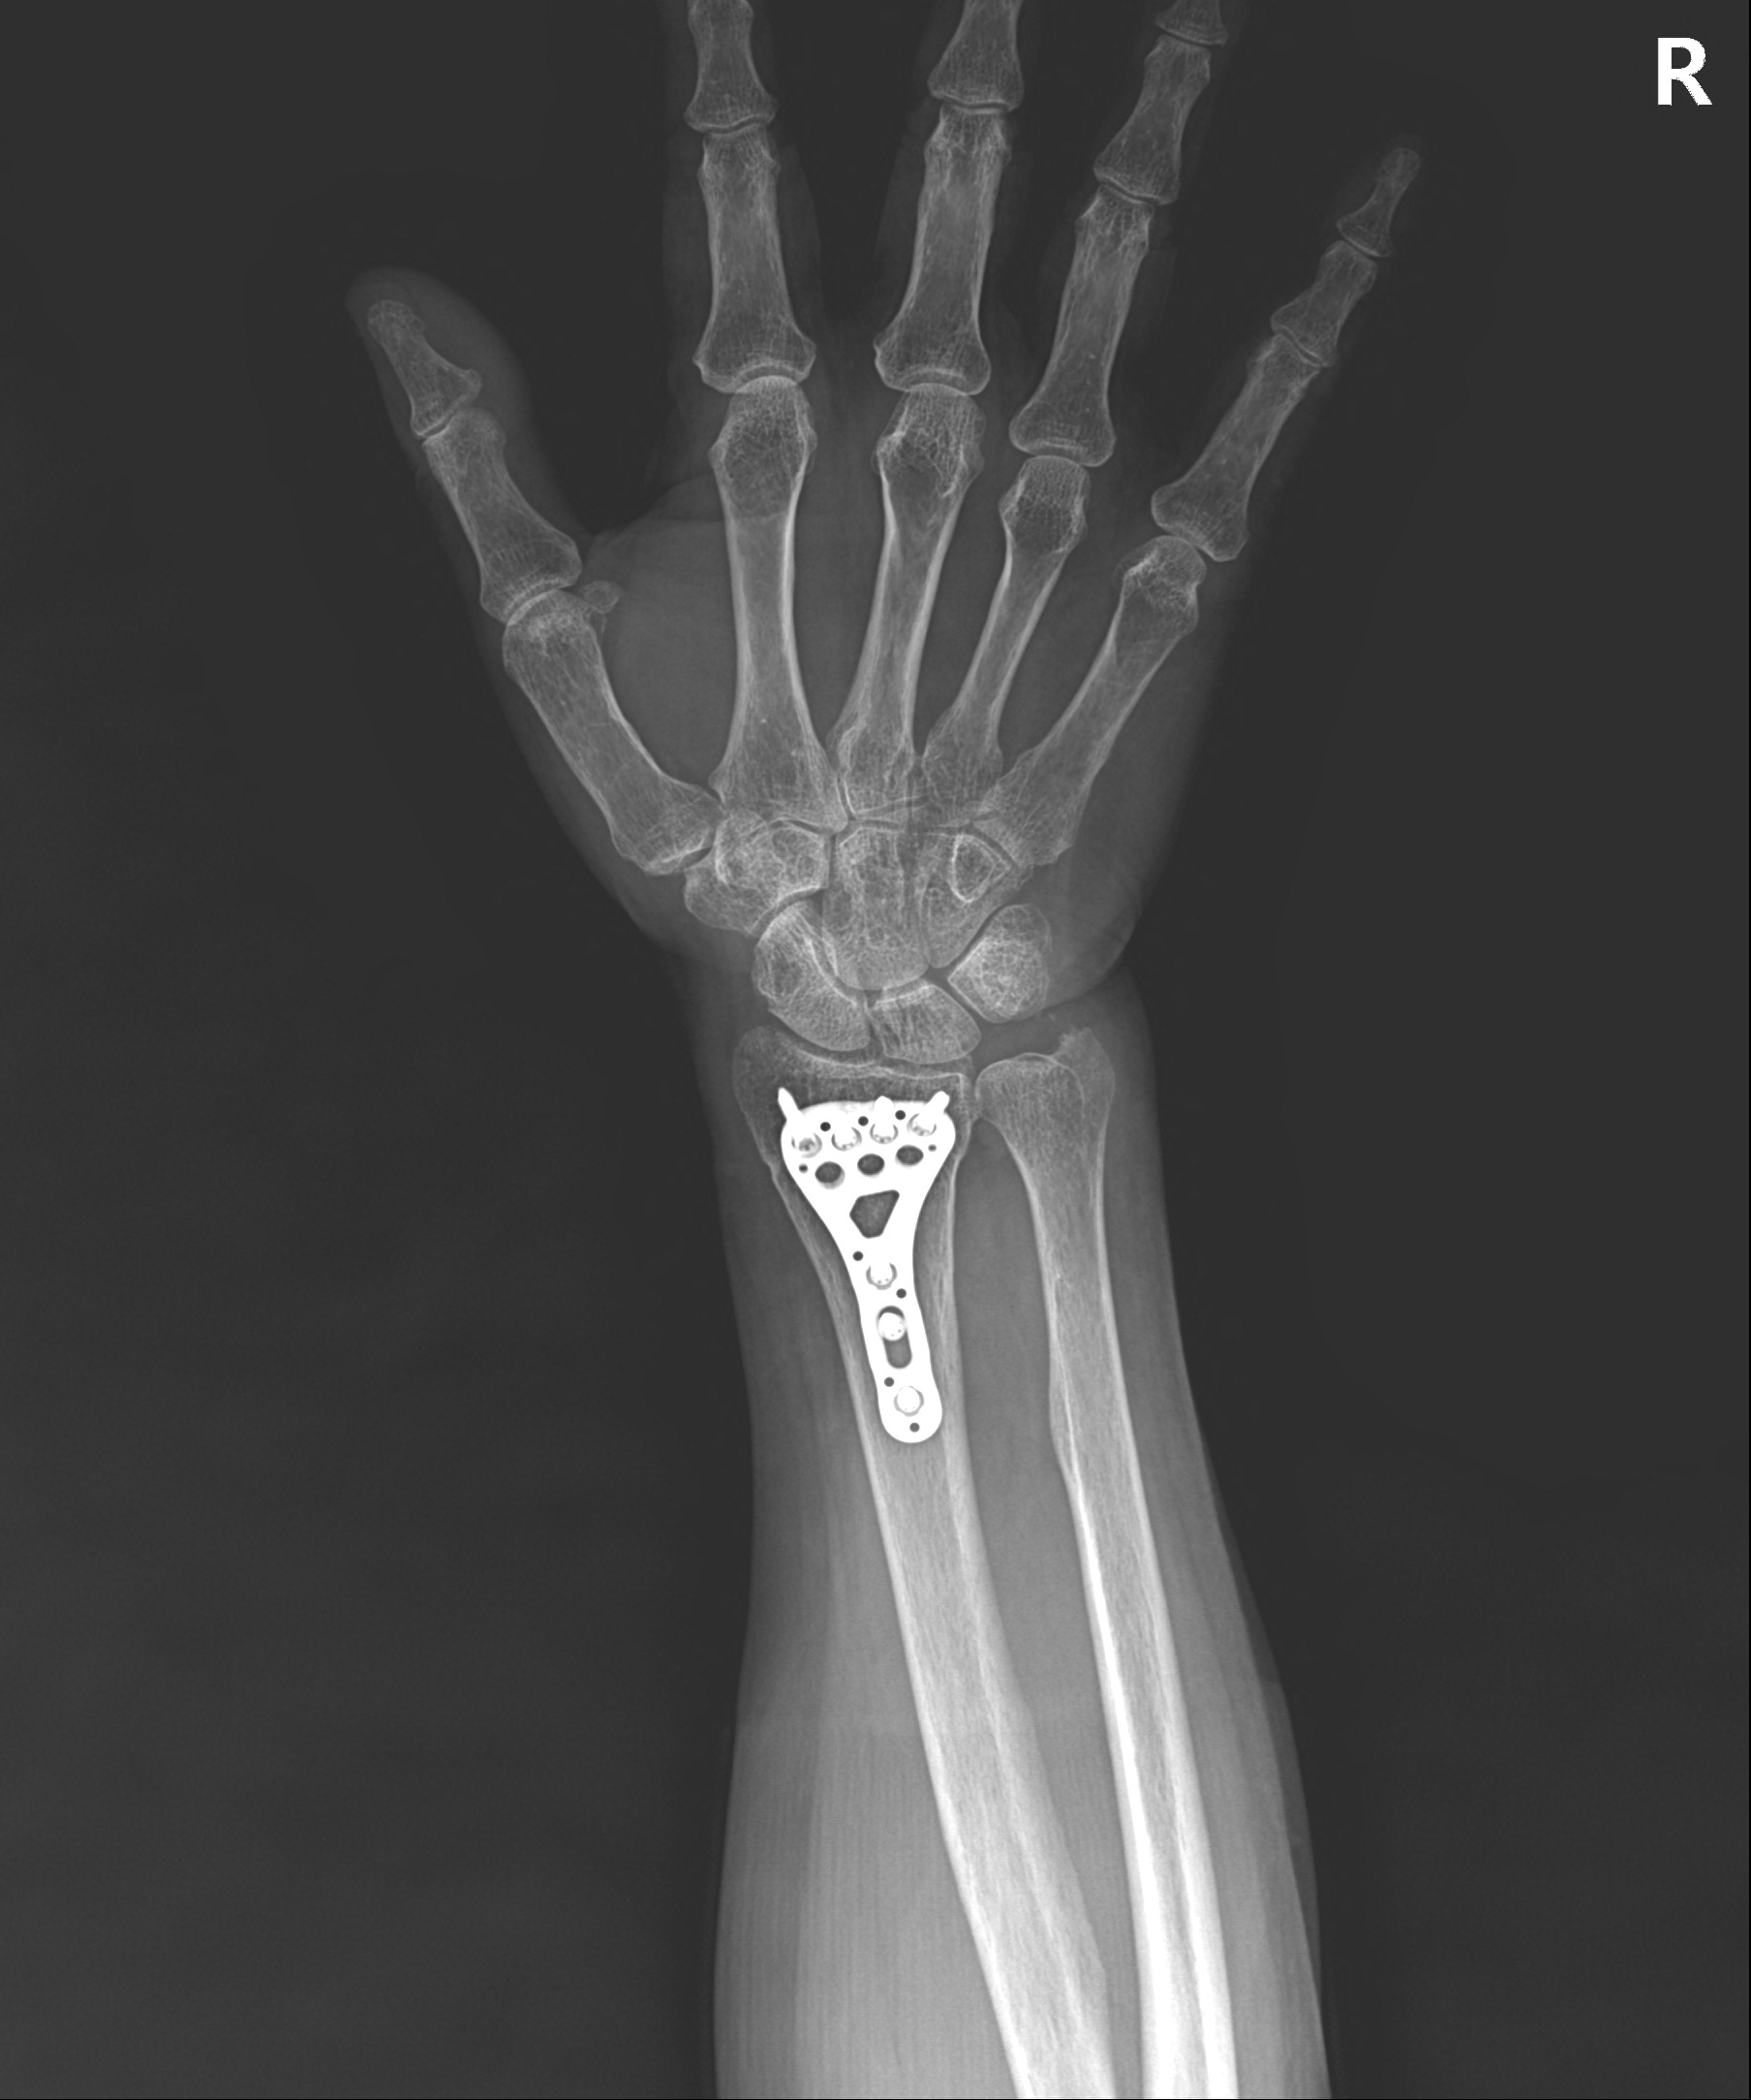

손목 골절 및 손가락 골절

대부분 손을 짚고 넘어지면서 발생하는 골절이고 다치면서 손등 쪽 뼈가 심하게 분쇄되는 경우가 많습니다.

골절 초기나 아니면 지연성으로 골절편이 손등 쪽으로 휘어져 변형이 발생하기 쉽습니다.

손목&손가락 골절에서 발생하는 문제점

□ 골절을 유합 시키기 위해 장기간 깁스를 할 경우 손목 관절이나 손가락 강직 발생

□ 손목 관절을 정확히 정복하지 못할 경우 외상성 관절염 발생 위험 높음

손목 골절

2023.01.04

2023.03.20